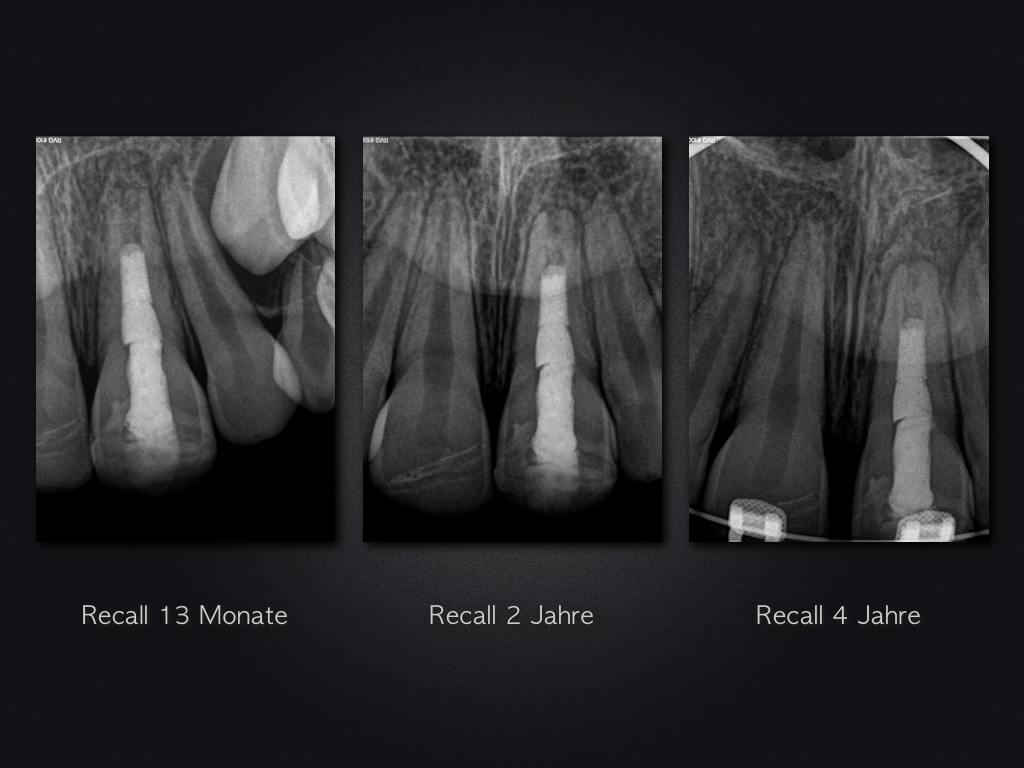

Revitalisierung – Recall nach 5,5 Jahren